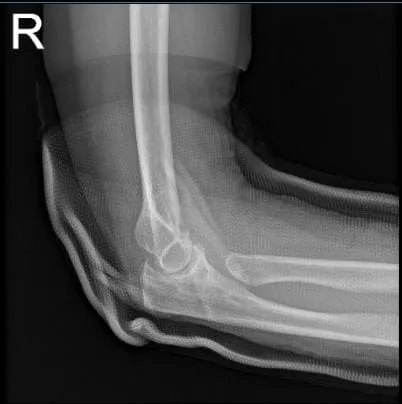

Ella trajo los resultados de radiografías del codo derecho y ha mostrado resección previa de la cabeza radial derecha. Cambios degenerativos osteoartríticos leves en el codo. En la radiografía de la muñeca derecha, mostró fractura distal conminuta del dije radial angulado.

Radiografía del codo derecho